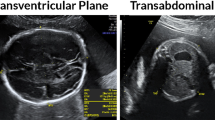

Acquisition of the fetal abdominal standard plane (FASP) is crucial for prenatal ultrasound diagnosis. However, it requires a thorough knowledge of human anatomy and substantial experience. In this paper, we propose an automatic method to localize the FASP from US images. Unlike the previous methods that consider simple low-level features such as Haar features, we exploited the deep convolutional neural network to automatically learn the latent representation. In addition, we adopted the novel knowledge transfer method to enhance the learning performance by making use of the knowledge obtained in other domain. Experimental results on 219 fetal abdomen videos showed that the classification accuracy of our method was above 90%, outperforming other methods by a significant margin.